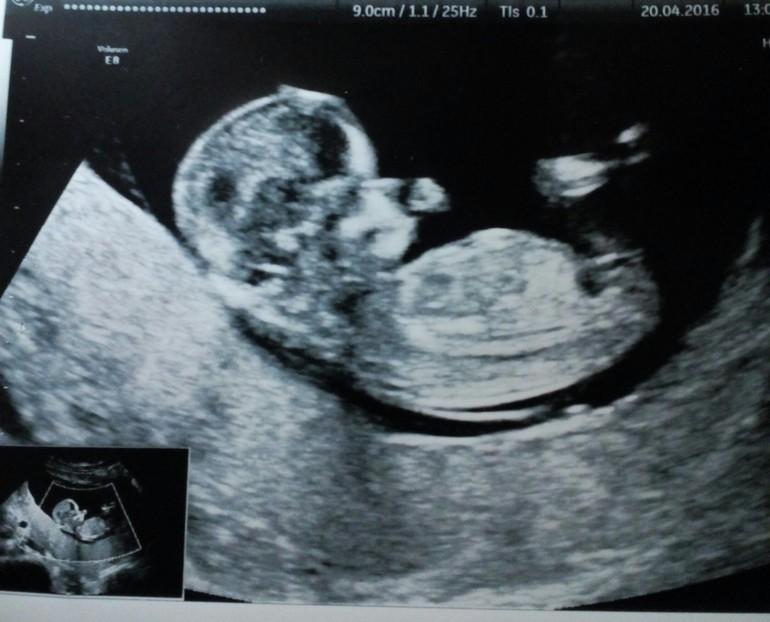

По УЗИ у нас вроде все отлично.Врач попалась в этот раз хорошая,показала нашу горошинку и даже фото сделала(для бесплатного УЗИ это роскошь)По приезду домой доченька сразу затребовала фото ляли и так рассматривала "мам,а это что у ляли?"," мам,а где сердечко?",это так мило.Дочка счатает что там определенно сестренка.

Напишу параметры,чтоб на память были:

КТР 58 мм

БР 17 мм

ОГ 65

ОЖ 57

ДБ 7,6 мм

ТВП 1 мм

Носовая кость 1,7 мм

ЧСС 158

Локализация по задней стенке матки

Заключение:беременость 12 нед. 5 дней

Предпологаемый срок родов: 28 октября

Вот она наша горошинка.

Мы с мужем угледели по фото,что это девочка.Посмотрим)